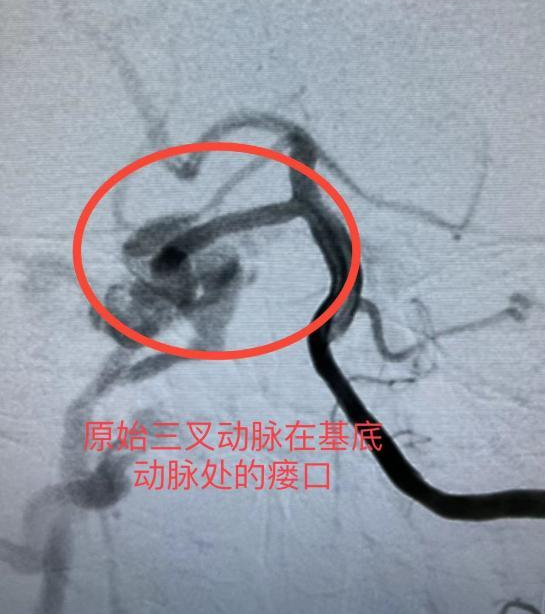

神经外科一区接诊医生李流清询问病史后,便为吴女士完善脑血管造影进行诊断。经神经外科一区专家评估,吴女士确诊为非常罕见的原始三叉动脉海绵窦瘘,Barrow分型B型,属于一种极为特殊类型的颈内动脉海绵窦瘘。若继续进展将出现球结膜充血水肿、颅神经麻痹症状,严重时导致失明。

神经外科一区主任张乃崇主任介绍,原始或者永存三叉动脉(persistenttrigeminalartery,PTA)是颈内动脉与基底动脉的胚胎性吻合血管,又名持续性三叉动脉或原始三叉动脉,属罕见的脑血管变异。在人类胚胎发育阶段,原始颈动脉与椎基底动脉系统之间有4支暂时性的通路,即原始三叉动脉、原始舌下动脉、原始内听动脉和原始寰前节间动脉(图12)。成人PTA发生率的统约为0.1%~1.0%,多为单侧发生,左右比例相同,女性多见。原始三叉动脉海绵窦瘘更是极为罕见,自1977年以来文献报道的只有20余例。临床上容易被误判为Barrow分型A型的颈内动脉海绵窦瘘,造成手术策略错误,瘘口栓塞不全。

在确认病情后,针对原始三叉动脉海绵窦瘘的治疗在粤西地区尚属首次,为了确保患者的安全以及手术的质量,医疗团队邀请了广东省人民医院脑血管病科的陈光忠教授前来共同讨论和分析病例。经过多次病例分析和术前讨论,反复推演术中可能出现的各种情况,并制定了详细的手术预案。在陈光忠教授的指导下,神经外科一区的手术团队密切配合,手术进行得紧张而有序,过程平稳顺利。仅用了50分钟,瘘口就被成功封堵,吴女士的颈内动脉和基底动脉得到了良好的保护,异常静脉及静脉窦的引流问题也得到了解决。

▲术前

术后